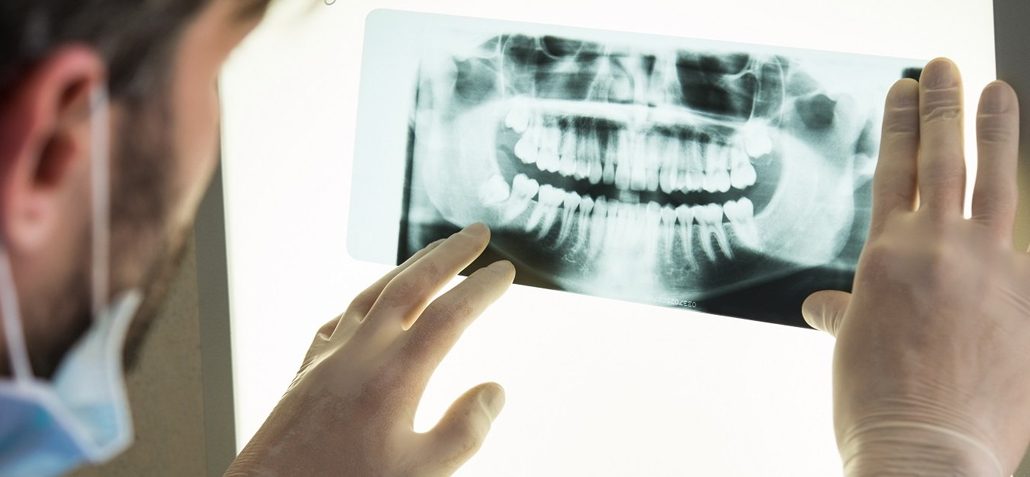

Stiamo ricercando in tutta Italia medici implantologi esperti in chirurgia all’on 4/6/8 a carico immediato. Si approfondiranno le esperienze chirurgiche del medico che risultando compatibile con il nostro progetto e le finalità chirurgiche, funzionali ed estetiche inizierà immediatamente a lavorare con noi operando i nostri pazienti.

Visita il nostro canale YouTube per visionare le tecniche chirurgiche da noi oggi erogate Canale Implantologia Network https://www.youtube.com/@Implana/videos